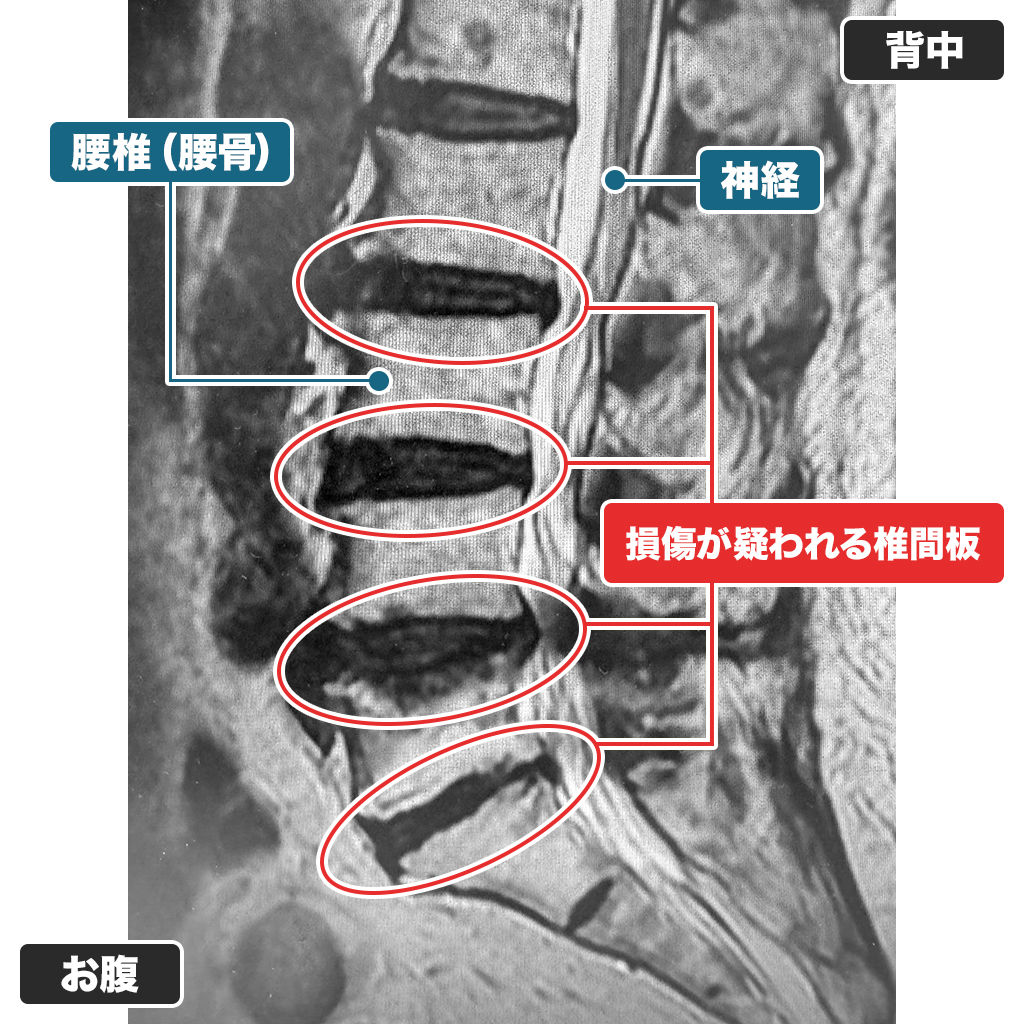

MRI検査

腰のMRI検査ですが、L4/5椎間板の容量は50%未満であり、腰椎もずれが確認され、腰椎すべり症と脊柱管狭窄症を合併されています。